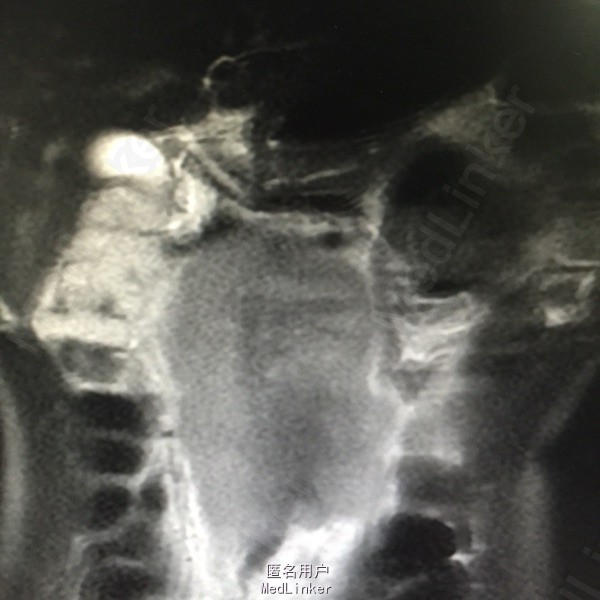

辅助检查:腹部MR:1.腹膜后占位(80*92*147cm),考虑淋巴瘤可能性大,病灶推压下腔静脉、门静脉主干及胰腺,包绕腹主动脉、肠系膜上动脉、双侧髂血管及双侧肾动脉,双侧肾静脉显示不清。2.肝左叶内胆管轻度扩张。胃镜示:1.慢性浅表性胃窦炎,2.胃窦粘膜隆起待查:异位胰腺?B超引导下行肿物穿刺活检术,病理结果示:符合生殖细胞来源恶性肿瘤,考虑精原细胞瘤可能性大。后完善盆腔CT示:1.右侧睾丸肿物,性质为恶性肿瘤,考虑为精原细胞瘤可能,阴囊右侧积液,腹膜后、肠系膜根部、盆腔内多发淋巴结转移,不除外累及胰头、体部、右侧腰大肌可能,下腔静脉、双侧髂总、内静脉、右髂外静脉、股静脉腔广泛栓子形成;盆腔少量积液。

患者3程化疗后复查CT评估PR:腹膜后大血管周围、盆腔内可见多发肿大淋巴结影,部分融合成团,最大层面范围为52*29cm,较前明显缩小。